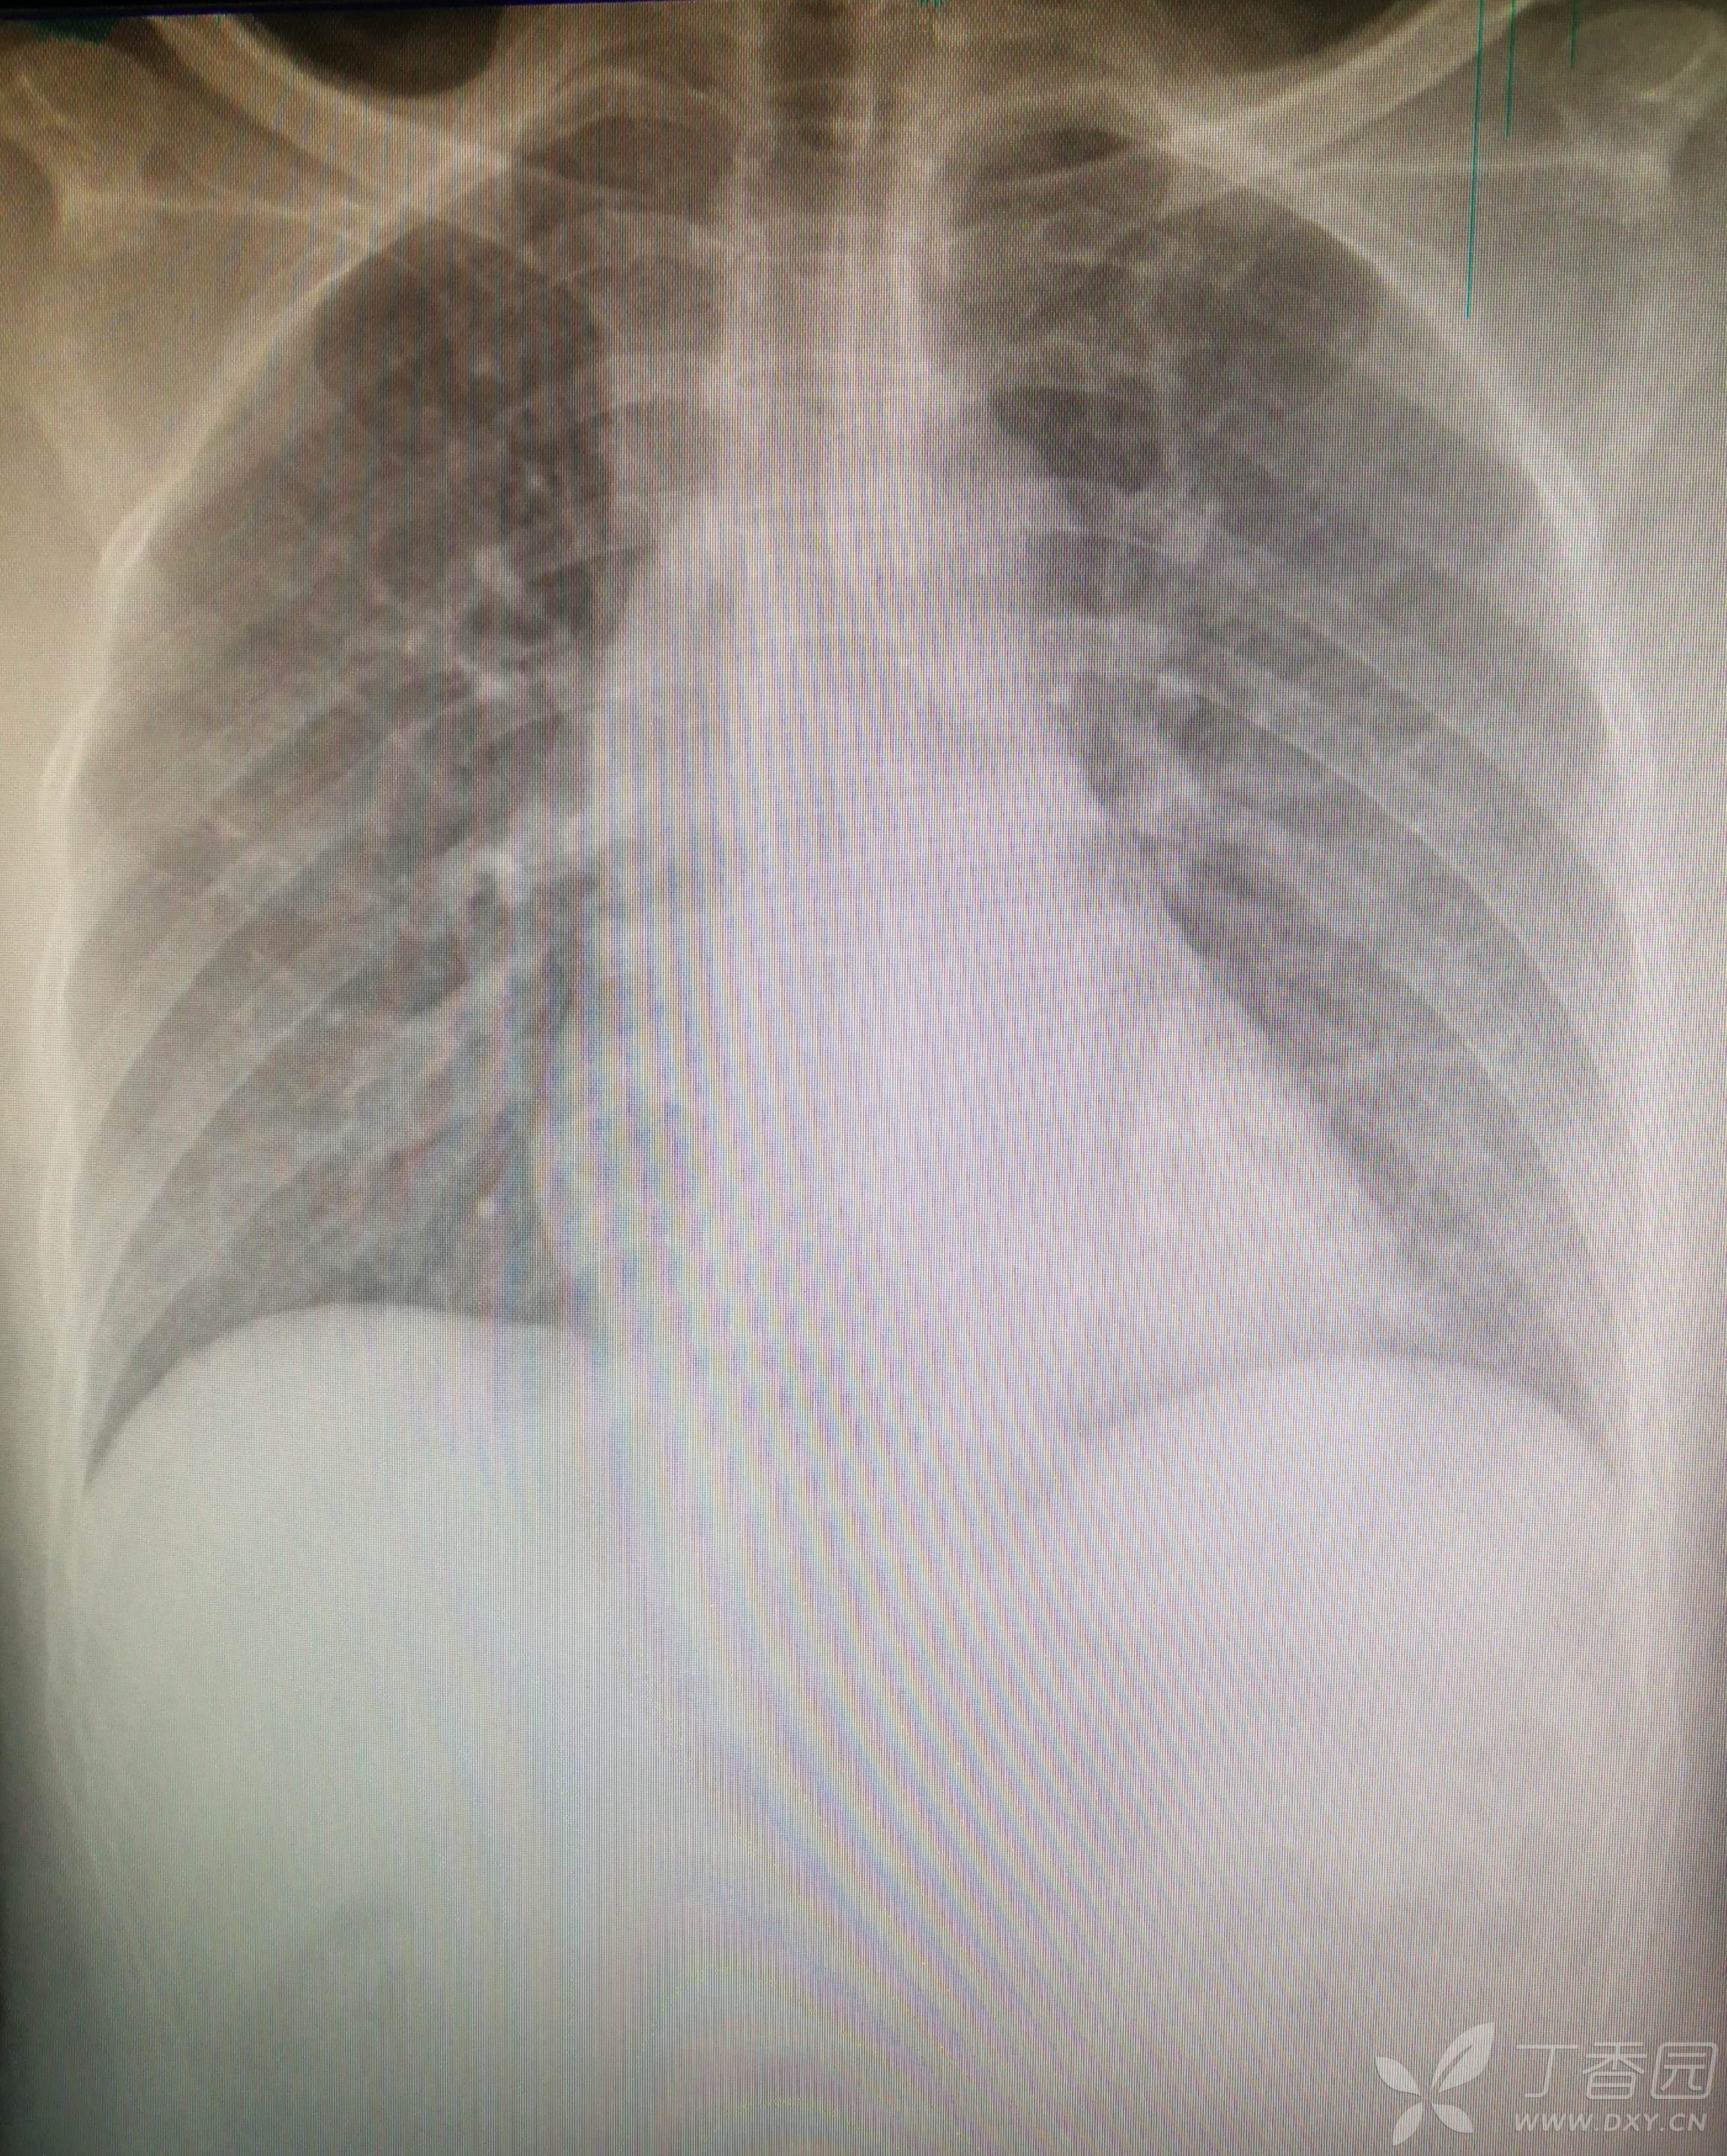

辅助检查:急诊X片:“左股骨下段粉碎性骨折”。急诊头颅CT:“左额颞部硬膜下少量积液”。急诊胸片: